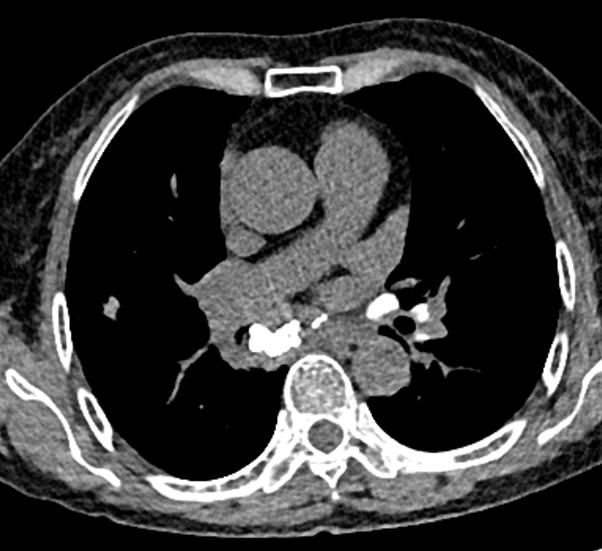

图10~图15 胸部CT示双肺多发钙化灶

问题出在哪儿?

右中间支气管的钙化病灶向外移动,钙化病灶的尖端刺激到支气管粘膜了(图16)。

图16 胸部CT

另外,这个患者的钙化灶非常危险,因为钙化灶的一端距离肺动脉才2毫米左右(图17),支气管镜下强行牵拉钙化病灶很可能会大出血危及生命。

图17 胸部CT